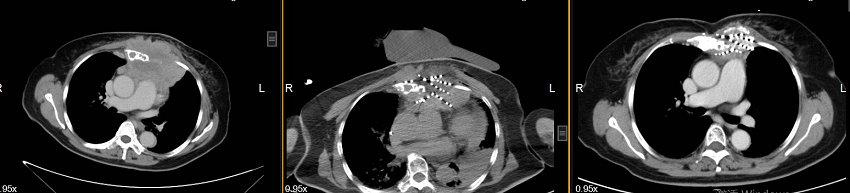

乳腺癌肺转移粒子植入治疗前、治疗中、治疗后1年对比